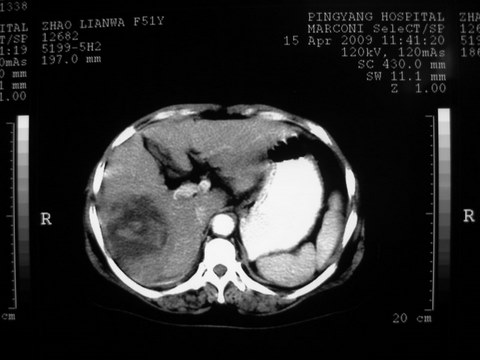

患者 女 51岁 两天前感觉上腹疼,无明显诱因,b超示肝右叶囊实性占位,边缘清楚,其内回声不均匀,ct增强如图,大家看看是什么 ,病人一年前及两月前b超检查只是提示胆囊炎

外院术后,证实肝癌合并出血

本例有2个特点:1,病灶发展迅速,(2月前正常)

2,囊实性,且并边界清晰光滑,呈右后叶赘生性。

可以排除源发肝脏恶性肿瘤和良性肿瘤。

只有转移,出血或炎症可以发展迅速!

特点:1,病灶发展迅速,(2月前正常)[br] 2,囊实性,且并边界清晰光滑,呈右后叶赘生性。囊性区无强化,实性部分较多轻度强化,边界欠清。考虑囊腺癌或囊腺瘤。

出病理 中分化肝细胞癌合并出血